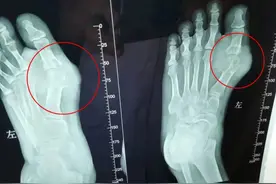

11月27日。陕西西安。一19岁男孩每天大量喝碳酸饮料造成脚趾关节红肿疼痛。前往西安市第五医院检查后确诊为痛风,并且有5*5公分大的痛风石。据悉,该男孩从很小的时候就开始爱喝碳酸饮料,平均每天喝3、4瓶,最多的时候一天喝7瓶饮料,1000多毫升。